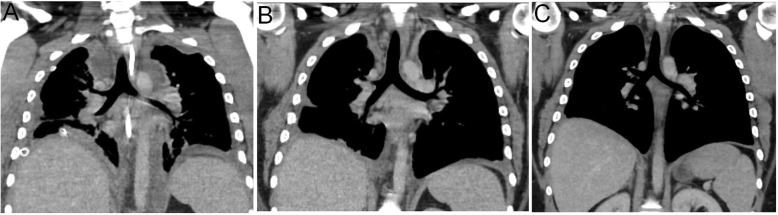

Blood cultures obtained systematically on days 8, 15 and 22 were negative. Subsequent echocardiography and chest CT-scan depicted the regression of both the mediastinal infiltration and residual abscesses (Fig. 3a and b). The patient was discharged from ICU on day 36 and from hospital on day 42 without any complication. Chest CT-scan performed two months later confirmed the complete disappearance of mediastinal abscesses (Fig. 3c).

Fig. 3.

(a) Day 7 CT scan- acme of the mediastinal infiltration, with abscesses formation (3 days after surgery); (b) CT scan at M1 after intensive care unit admission; (c) CT scan at M2 after intensive care unit admission